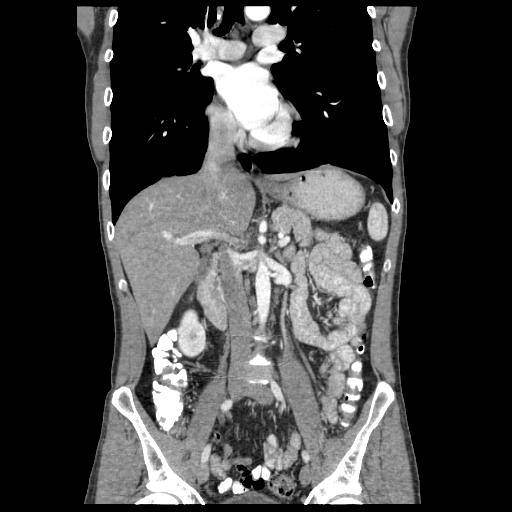

КТ брюшной полости с контрастом

Единственный в Москве компьютерный томограф Revolution CT (GE)

512 срезов

• Высокая экспертиза: мы провели более 11.000 исследований за 2019-2020г.

• Диагностика изменений в органах на самых ранних стадиях

• Заключение в течение 2-х часов

• Проводим детям и взрослым

• Высочайшая скорость и точность сканирования

• Визуализация мельчайших образований до 3,0 мм

• Минимальная лучевая нагрузка (в 4 раза меньше, по сравнению с аппаратом 16 срезов)

• До 220 кг

КТ брюшной полости с контрастомОптимальным диагностическим методом, позволяющим получить максимально подробную и точную информацию о состоянии внутренних органов, служит КТ с контрастом брюшной полости. Исследование позволяет при помощи 3D визуализации выявлять даже небольшие изменения в структуре тканей, на основе полученной картины устанавливать точный диагноз и назначать оптимальное лечение пациента. Введение контрастного препарата на основе соединений йода повышает четкость и информативность изображений. Вещество с неодинаковой скоростью проникает и накапливается в разных типах тканей, благодаря чему патологически измененные участки органов становятся намного более заметными.